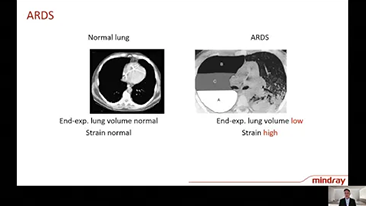

Dengan wawasan mendalam tentang kebutuhan klinis pasien dan perawat, ventilator Mindray mendukung kebutuhan terapi berurutan antara terapi oksigen, ventilasi non-invasif, dan ventilasi invasif dengan kinerja stabil, fungsi serbaguna, dan kemudahan penggunaan. Mode ventilasi dan alat pendukung pengambilan keputusan dikembangkan berdasarkan kebutuhan klinis dan pedoman profesional, untuk membantu petugas medis mengambil keputusan klinis dengan tenang pada semua populasi dan tingkat ketajaman pasien.

Memilih pengaturan ventilator yang tepat untuk pengobatan pasien dengan penyakit saluran pernapasan merupakan masalah yang cukup penting. Karena tugas menentukan parameter peralatan ventilasi sepenuhnya dilakukan oleh dokter, pengetahuan dan pengalaman dokter dalam pemilihan pengaturan ini memiliki efek langsung pada keakuratan keputusannya. Paradigma perawatan suportif pasien telah berubah secara signifikan selama 20 tahun terakhir. Saat ini, berbagai mode ventilasi dan alat pendukung keputusan telah dikembangkan seputar kebutuhan klinis untuk membantu membantu pengasuh meningkatkan efisiensi dan menghilangkan kesalahan dalam keputusan klinis.